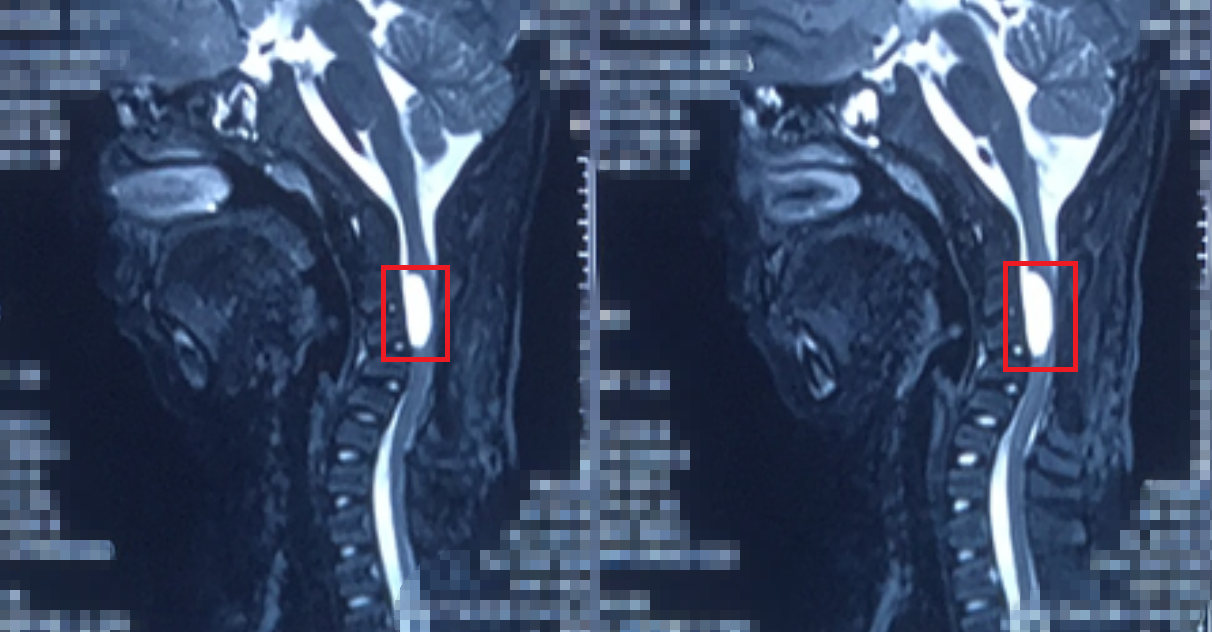

来我院前复查,囊肿(红框内)仍然在,颈椎已出现严重的后凸(反曲)畸形,孩子四肢无力,上肢不能持物,下肢不能行走

脊髓被囊肿压迫得还剩一个薄片